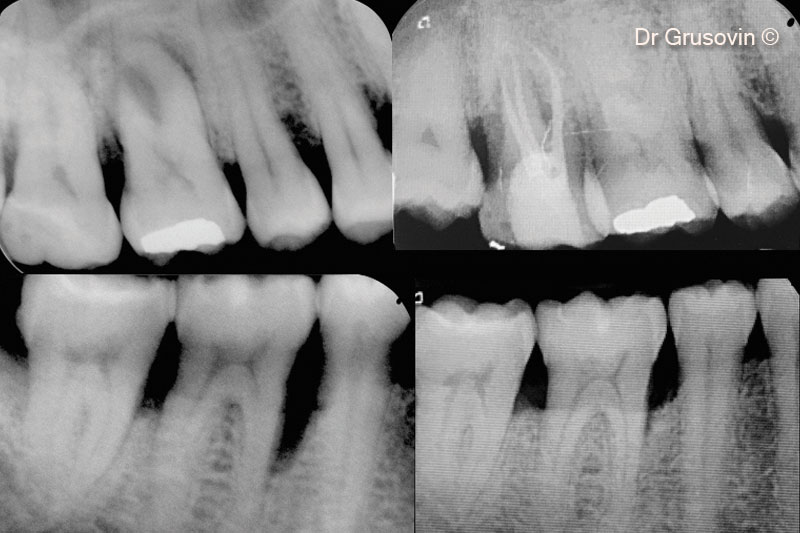

Chụp X-quang sau 1 năm theo dõi.

Sự hình thành xương ở khuyết tật chẽ chân răng số 16 sau 1 năm theo dõi.

Ảnh chụp X-quang #46

Ảnh chụp X-quang trước và sau 7 năm theo dõi.